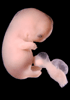

Carnegie Stage 19 (47 post-ovulatory days)

Most embryos at stage 19 are approximately 47-48 post-ovulatory days old and measure 17-20 mm in length. Distinguishing criteria for this stage include straightening of the trunk, the limbs extend nearly directly forward, toe rays are prominent, but interdigital notches have not yet appeared in the foot.

Although some of the photographs below show abnormal embryos, the animations and MRI slice images all depict normal embryos. Abnormal embryos are noted in the titles of the large photos when they are opened.